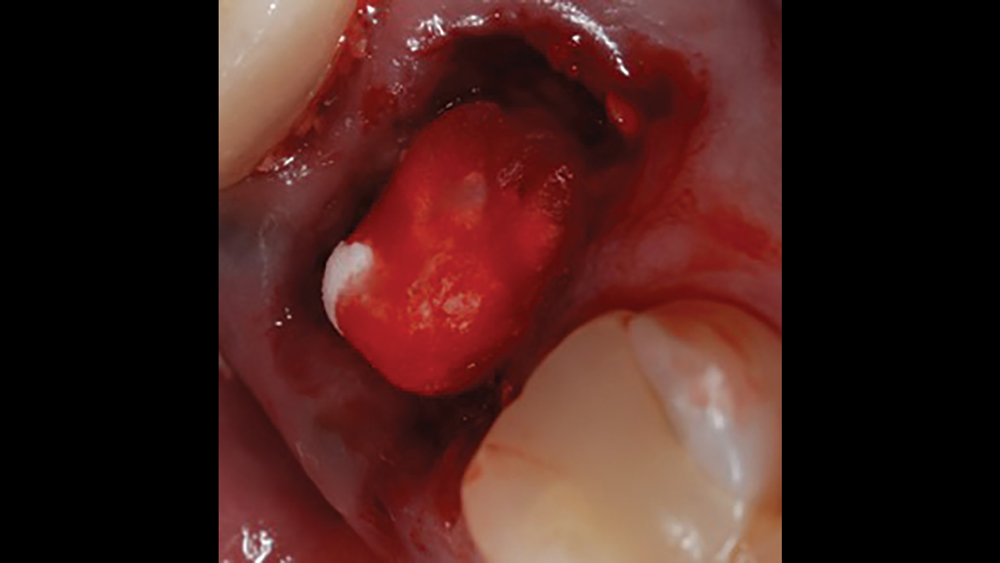

a. Collagen plugs are mainly used to control bleeding and maintain the blood clot within extraction sites (Figs. 5a, 5b). Collagen plugs are usually a soft, pliable, sponge-like material that rapidly absorbs blood, thereby creating an artificial clot. The collagen allows aggregation of platelets, which results in the degranulation and release of bone-growth factors. Collagen plugs have a resorption time of approximately 10–14 days.

Figure 5a: Newport Biologics Resorbable Collagen plug is used

Figure 5b: The plug helps control bleeding and maintain the blood clot in the extraction site

Figures 5a, 5b: Used to control bleeding and maintain the blood clot within the extraction site, the Newport Biologics™ Resorbable Collagen Plug (Glidewell Direct; Irvine, Calif.) supports predictable bone regeneration.